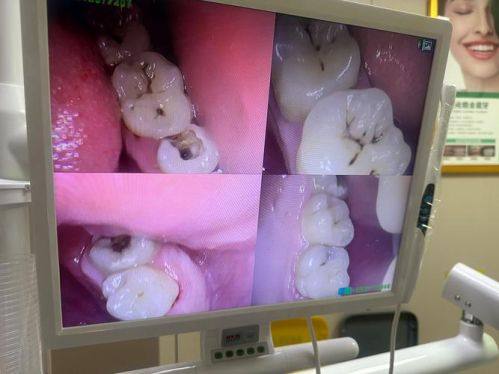

2. 智能化影像系统:辅助诊断,提高诊断的正确性和效率。